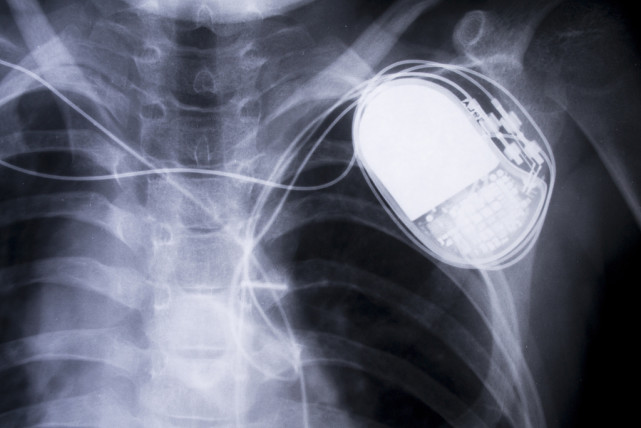

人工心脏起搏器,主要包括脉冲发生器、起搏电极导线、阳极和阴极组成一对电偶以及电回路等结构。

这是人工心脏起搏器的外观:

这是人工心脏起搏器的体内部分安装位置: